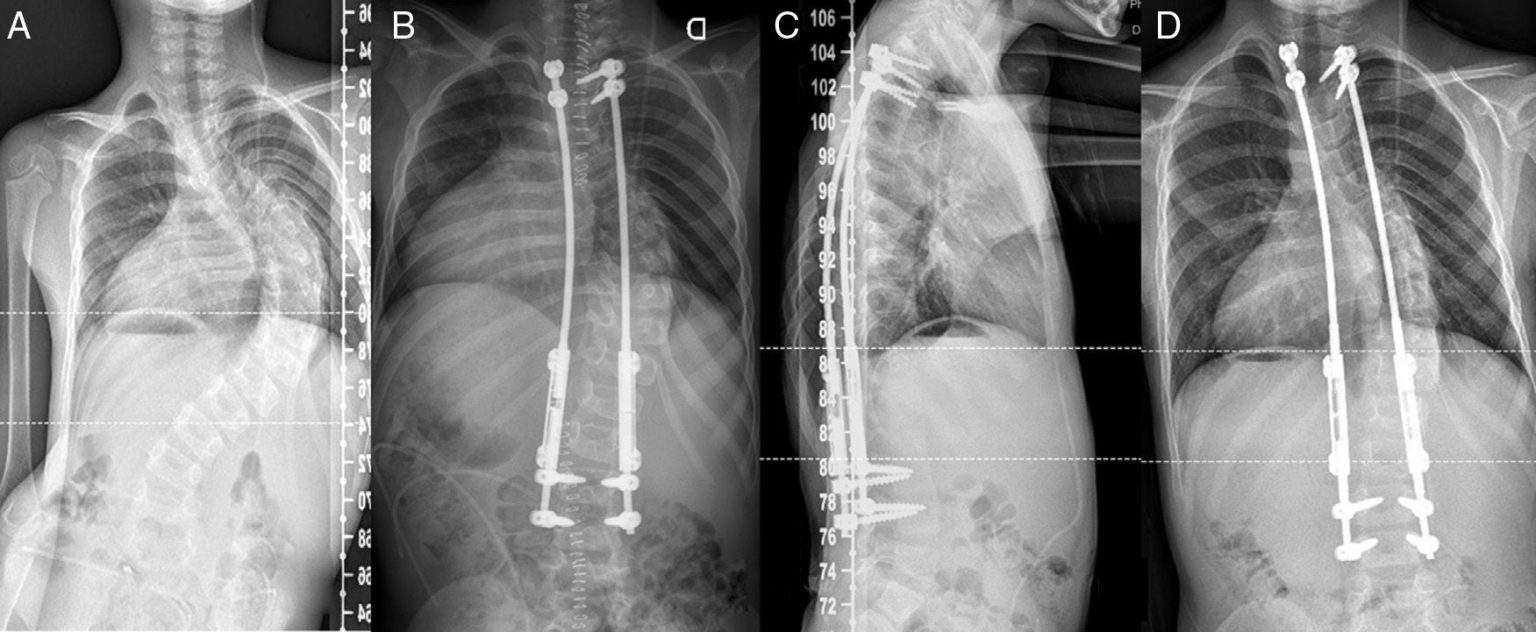

مدیریت درد، کنترل خونریزی و بهینهسازی تغذیه در جراحی اصلاح انحراف و ناهنجاری ستون فقرات مقدمه جراحیهای اصلاح انحراف ستون فقرات مانند اسکولیوز، کیفوز ... ادامه مطلب